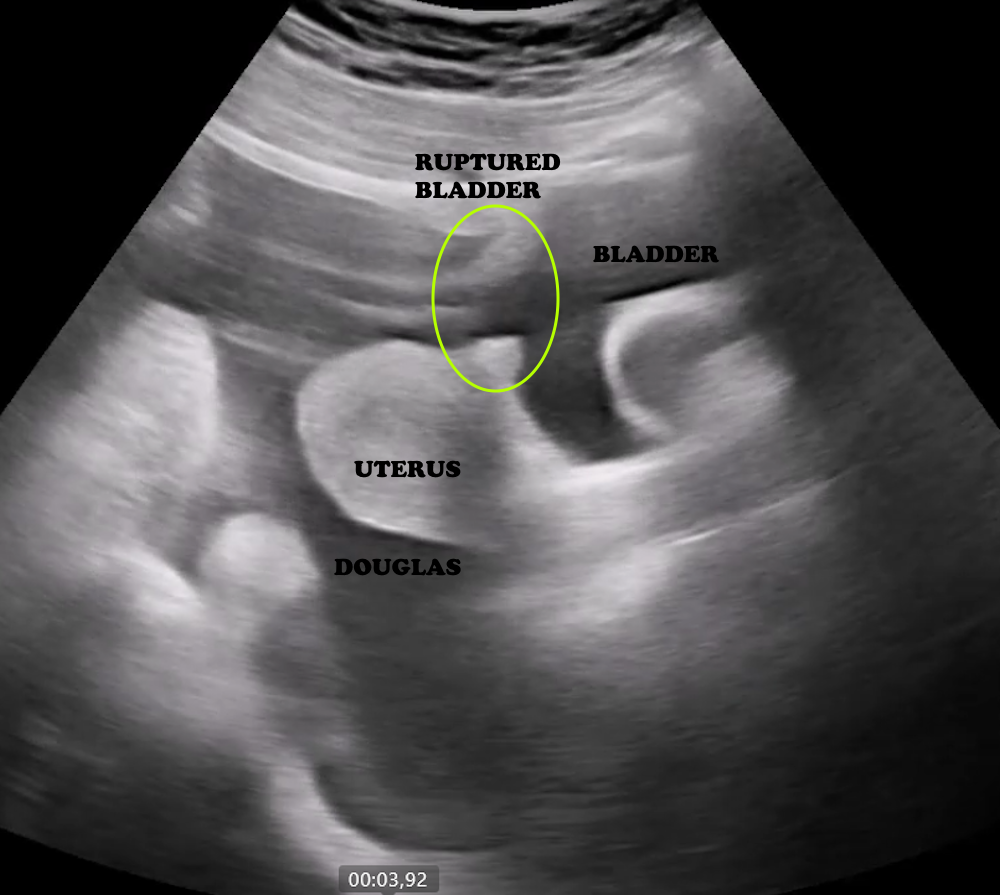

The bladder is located in the pelvis, posterior to the symphysis pubis, and is evaluated using a transabdominal approach. The best images are obtained when the bladder is moderately filled. The probe is placed on the lower abdominal wall, in contact with the pubic bone. Imaging should be performed in both transverse and sagittal planes.

The bladder lumen appears anechoic, while the walls are smooth and hypoechoic (Figure 18).In female patients, pelvic ultrasound also includes the evaluation of the uterus and ovaries (Figure 18). The uterus is recognized by its characteristic “double line” appearance, and in pregnancy, the embryo may be visualized (Figure 19).

Bladder rupture is identified by irregularity of the wall and the presence of extraluminal fluid accumulation (Figure 20).